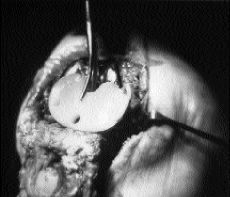

En Agosto de 1992 la enferma sufre una caída golpeándose con las rodillas en el suelo; acudió al Servicio de Urgencias, donde se practicaron radiografías, no apreciando anomalías e instaurando tratamiento conservador. Desde el momento de la caída la rodilla derecha se vuelve dolorosa, con episodios de tumefacción y sensación de inestabilidad; es seguida mediante controles sucesivos hasta Mayo de 1993 en que se aprecia subluxación del componente femoral y tibial (Fig. 2), indicándose artroplastia de revisión. Un mes más tarde se realiza esta cirugía utilizando una prótesis tipo AGC-2000. Se realizó una V cuadricipital para una buena exposición y se comprobó el buen estado de la rótula y del componente femoral, una intensa metalosis sinovial junto con la usura y rotura del polietileno en su zona posteromedial (Fig. 3), al igual que la rotura en la misma zona de la bandeja metálica (Fig. 4). El LCP estaba conservado y el platillo tibial interno hundido, por lo que se elevó el hundimiento mediante homoinjerto liofilizado utilizando cresta ilíaca y mezcla de «chips» de esponjosa y polvo de cortical hasta rellenar el defecto. Se respetó la rótula y se cambiaron los componentes femoral y tibial, ya que el primero no era compatible con la nueva base tibial. Se utilizó un polietileno de 14 mm de grosor con vástago de revisión central y cilíndrico de 80 mm y dos tornillos de 25 mm. Los cultivos de las muestras obtenidas durante la intervención fueron negativos y el postoperatorio fue normal, dándose de alta a las 2 semanas con una extensión completa y una flexión de 70°. Se decidió una descarga parcial durante

Figura 3. Metalosis sinovial junto a usura y rotura posteromedial del polietileno.

La sinovial presentaba un aspecto de inflamación crónica con restos de partículas metálicas y de polietileno (Fig. 4) debido a que se había roto tanto el metal como el polietileno. Coincidiendo con otros autores,9,13podría ser que esta inflamación influyera en el aflojamiento de la bandeja al favorecer una membrana en la interfase hueso-cemento y la destrucción quística del hueso que soporta la bandeja. Ambos procesos aumentarían, por tanto, el estrés que soporta el platillo tibial.